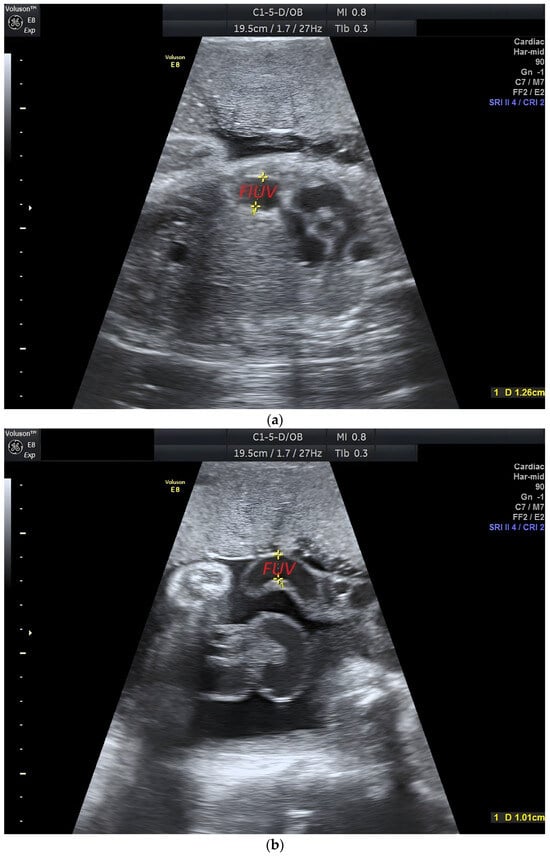

2. Case Report